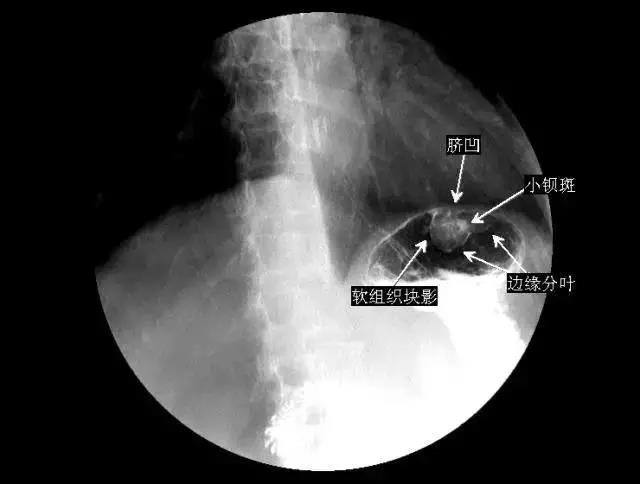

1、非小细胞肺癌是指除小细胞肺癌外,其他病理类型的肺癌总称肺癌根据病理特征可分为两大类小细胞肺癌和非小细胞肺癌小细胞肺癌因恶性程度极高早期易转移预后极差,被单独归类而腺癌鳞癌大细胞癌及其他罕见病理类型则统称为非小细胞...